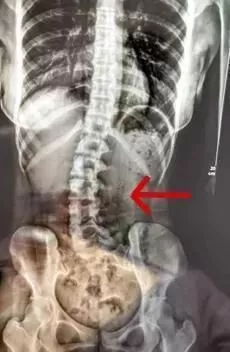

“正值18岁的女生小邹(化名),经常因腰痛、脖子酸等症状,并且情况逐渐严重。于是来到医院就诊,医生检查发现脊柱严重侧弯,经过x光检查,发现她的腰椎向右侧弯、旋转,并以腰2椎体为中心向右侧弯,脊柱向右发生明显侧弯。”

d2.webp 小邹的脊柱明显侧弯 广医三院图医生经过问诊后发现竟是因为 她的睡眠姿势不对。小邹长时间侧躺睡而且是侧同一边,并且下腿摆姿不正确。“患者是因为其睡姿不当,原有正常的脊柱体态在日积月累的错误睡姿中逐渐失衡,骨盆与脊柱位置变化,脊柱就发生了侧弯。”广州医科大学附属第三医院中医科主任医师胥海斌介绍。